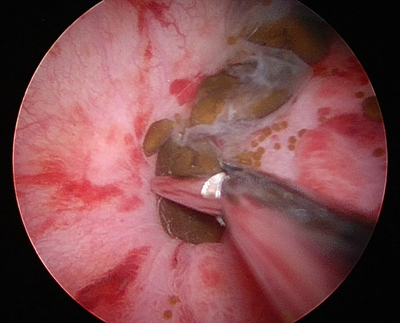

5㎜以上など吸引が出来ない結石は鉗子と呼ばれる器具で実際に掴んで体外へ牽引します。この場合には一度に一つしか掴むことが出来ないために一つずつ摘出することになります。

鉗子による結石の把持